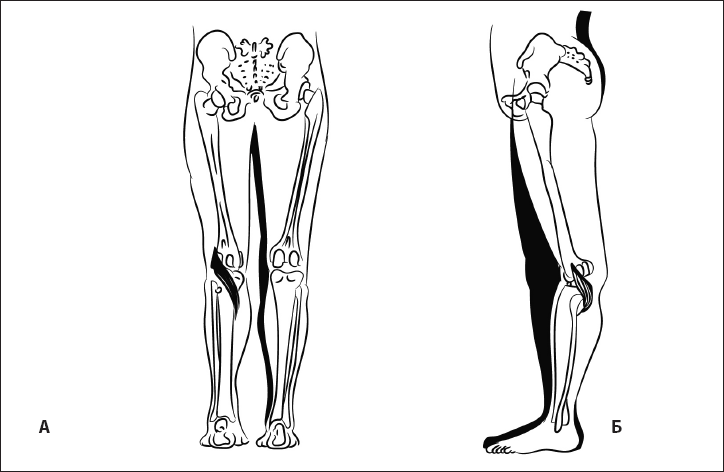

Рис. 33. Флексия бедра и смещение коленного сустава внутрь при укорочении мышцы, напрягающей широкую фасцию бедра. А – вид сбоку, Б – вид спереди.

Рис. 34. Флексия бедра и смещение коленного сустава кнаружи при укорочении приводящих мышц. А – вид сбоку, Б – вид спереди.